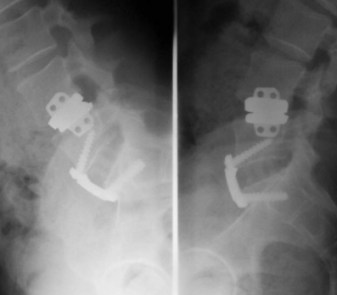

Let’s see : The disc prosthesis is a minimally invasive surgery

– To restore disc height

– To restore foraminal height

– To restore sagittal balance

– To restore the function of the intervertebral disc

– To protect the lumbar muscles

– To avoid the passage into the spinal canal